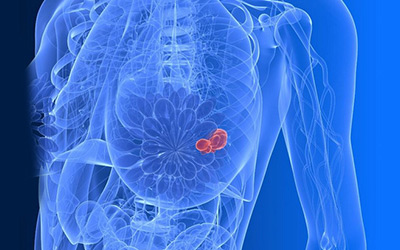

中国城市儿童恶性肿瘤发病率上升18.8%

据世界卫生组织(WHO)资料显示,恶性肿瘤已成为儿童第二大死因,软组织肉瘤已成为儿童癌症致死的第5位病种。近5年来,中国城市儿童恶性肿瘤的发病率上升了18.8%,远高于发达国家,据估算,每年新发病例可达4000—5000例。

去年中山新发乳腺癌约五六百例,呈逐年上升趋势

“乳腺癌是所有癌症中治疗效果最好的一种,95% 以上的乳腺癌患者都可以完成治疗,目前中晚期病人已经转成慢性疾病的治疗。只要早发现早治疗,早期病人5 年生存率可达90% 以上。”